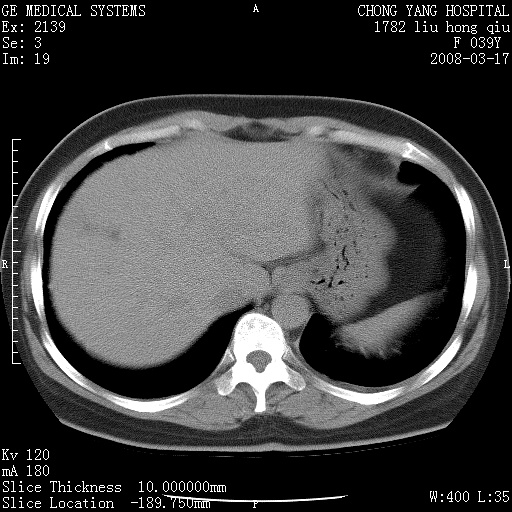

以下是引用yangxue121在2008-5-31 20:24:00的发言:[br]考虑多发胸膜间皮瘤[br]左侧少量胸腔积液[br]肝脏密度不均

以下是引用长城干红在2008-5-31 21:42:00的发言:[br]肝脏密度不均,建议增强扫描,胸膜下多发结节,考虑为胸膜来源的原发肿瘤或转移瘤。